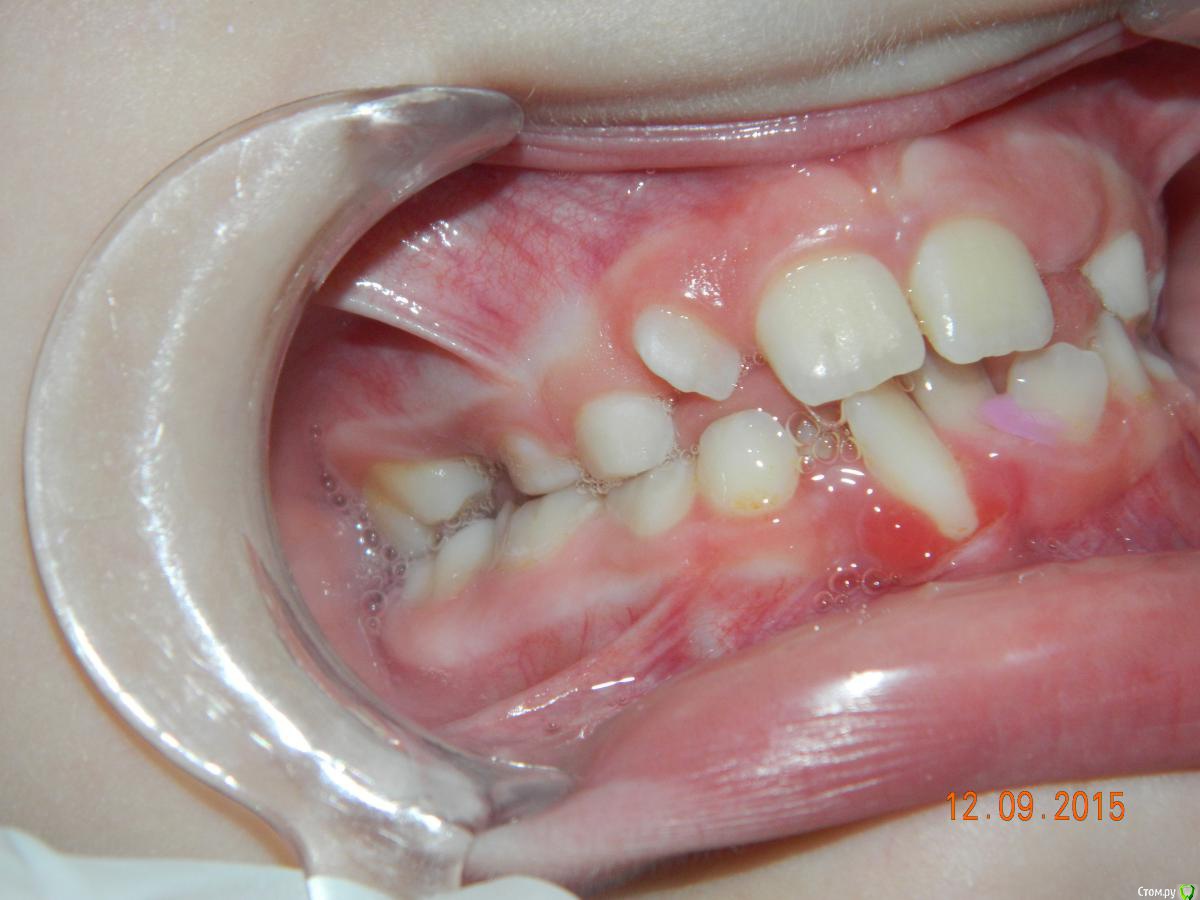

yakinanata Опубликовано 15 сентября, 2015 Поделиться Опубликовано 15 сентября, 2015 Добрый день. У девочки 7 лет в области 41 зуба рецессия десны, десна гиперемирована, гипертрофирована (как "цветочек"), болезненная, зуб интактный, неподвижный. Обратились за ортодонтической помощью, так-как выраженная скученность передних верхних и нижних зубов. Хотят выровнять зубы, так-как считают, что воспаление десны от скученности. Есть вредная привычка грызть карандаши, ручки. Попросила показать, кусает на 31, и мама говорит, что "вроде бы грызет с другой стороны". Девочку беспокоит это давно, лечение никакое не проводили. Ранее травмы не было. Позже принесут ОПТГ, может что-то там будет интересное?Буквально за день до них лечила мальчика 6 лет и заметила у него похожую картину. Рецессия десны в области 41, слизистая бледно розовая. Зуб 41 подивжен 1 степени, имеется гипоплазия на вестибулярной поверхности. Между 41 и 31 диастема, 82 зуб отсутствует, этот 41 зуб как-бы "одинокий такой, без поддержки". Ранее была травма 81, после которой началась рецессия и зуб удалили. Снимок сделать не удалось и фото тоже. Мне интересно, сталкивался кто-нибудь с этим? каковы возможные причины? лечение? Начинать ли ортолечение? Планировала трейнер, боюсь, десне это не понравится. Ссылка на комментарий